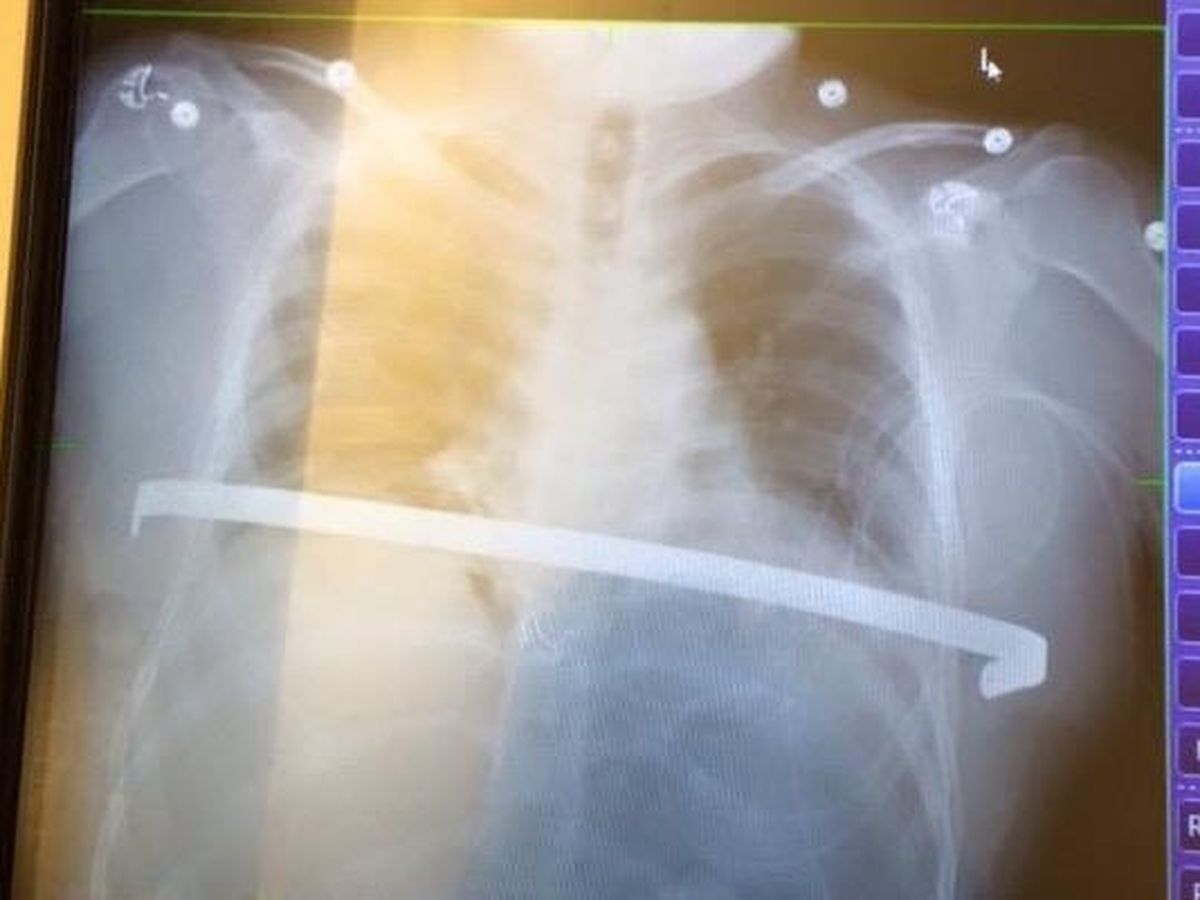

Josh was born with a condition known as pectus excavatum. It is a condition in which a person's breastbone is sunken into one's chest. Severe cases of pectus excavatum can eventually interfere with the function of the heart and lungs. Josh's case was so severe that three years ago it was determined he needed what is called a Nuss Procedure, whereby one to three curved metal bars are inserted behind the sternum in order to push it into a normal position. In this surgery they make a tunnel under your rib cage and over your lungs and heart so that a pre-bent bar can be inserted flat, attached to the side of the ribs, and cranked up to micro fracture all of the ribs and sternum, while at the same time supporting the rib cage so that it is able to heal in the correct form to allow the heart and lungs to function properly. The bars are then left in for a period of three years at which time they need removed. As you can imagine it is an extremely painful process, and despite many setbacks since having it done, Josh has not given up and continues to fight. The procedure Josh currently needs done is to have those bars removed. The total cost is approximately $17,000 and he has an immediate deductible to pay for $2000.00 in order to proceed. Thank you in advance for any contribution you may wish to offer and God bless. You are much appreciated.